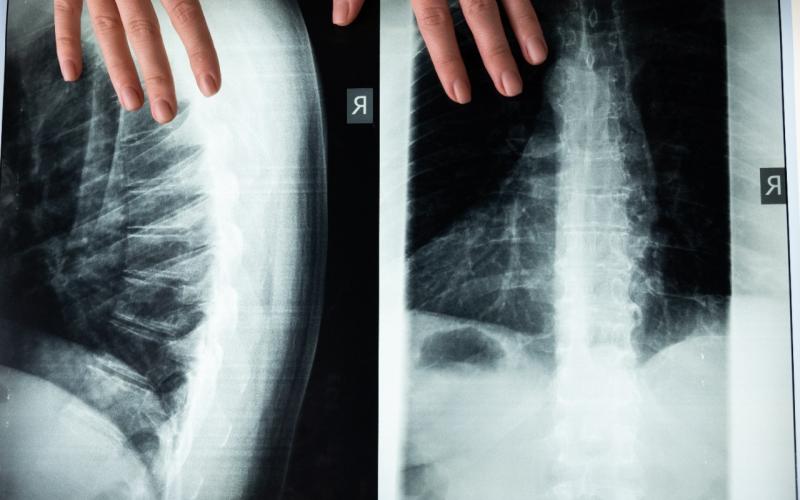

El examen puede complementarse con un ultrasonido dentro del primer mes de vida y después del mes con estudios radiológicos de pelvis y proyecciones especiales, dentro de los signos clínicos puede evidenciarse discrepancia de miembros que uno o ambos miembros sean más cortos, asimetría de pliegues, limitación de la abducción de la cadera y signos clínicos como el Barlow y el Ortolani.